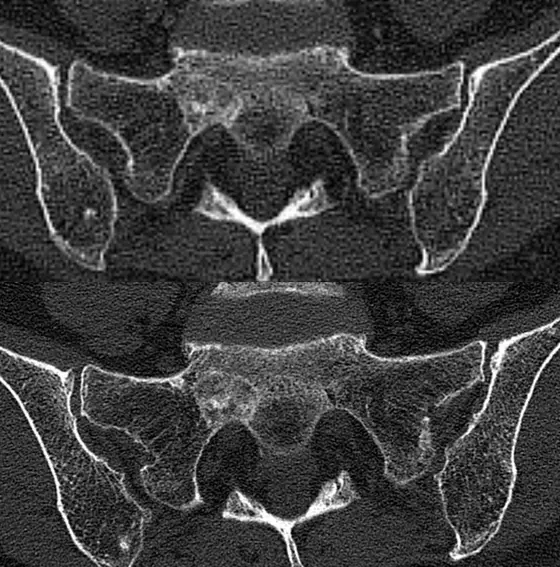

Aufnahme des Beckens einer Brustkrebspatientin mit Knochenmetastasen. Oben: Konventionelle CT-Aufnahme, unten: Photon-Counting CT

In der aktuellen Studie wurden die PC-CT-Bilder von Knochenmetastasen bei Patientinnen mit fortgeschrittenen Brustkrebserkrankungen von mehreren Ärzten beurteilt und mit konventionellen CT-Aufnahmen verglichen. Die mithilfe der neuen Technik generierten Bilder wurden durchgehend als schärfer und detailreicher beurteilt. Insbesondere Veränderungen an sehr feinen Strukturen wie etwa den Knochenbälkchen (Trabekeln) waren besser zu erkennen.